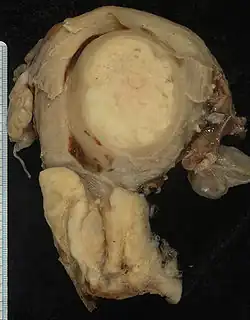

Frequentemente, antes da biópsia, o médico solicita exames de imagem para descartar outras causas para os sintomas da paciente. Algumas modalidades de imagem incluem a ultrassonografia, a tomografia computadorizada e a ressonância nuclear magnética, que têm sido usadas na busca por outras doenças, para identificar extensão do tumor e seu efeito sobre estruturas adjacentes. Tipicamente, o tumor se apresenta como uma massa heterogênea no colo.[35]

Os subtipos histológicos do carcinoma invasivo do colo do útero são:[38][39]

- carcinoma de células escamosas

- adenocarcinoma (cerca de 15% dos cânceres do colo do útero no Reino Unido)[36]

Embora o carcinoma de células escamosas seja o tipo mais comum, a incidência do adenocarcinoma do colo do útero tem aumentado nas últimas décadas.[4]